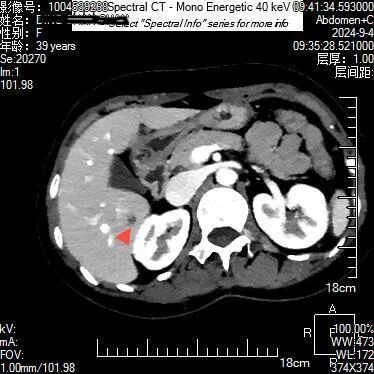

上腹部隐痛不适半个月,在当地医院就诊未发现明显异常,患者到贵州航天医院就诊,被检出肝脏肿瘤性病变,得到了及时诊治。 近日,一位39岁的女性患者在贵州航天医院就诊,通过该院最新引进的贵州首台飞利浦皓克双层探测器光谱CT,进行高精度扫描,该院医师利用光谱CT多参数能谱数据分析中的单能40KeV、碘密度图及有效原子序数功能,对患者进行了细致分析,医师在患者肝脏S6段发现一隐匿性肿瘤性病变,患者得以早期发现及时治疗。 采用光谱有效原子序数图 贵州航天医院医学影像科主任余雷向记者介绍,这个病例凸显了飞利浦皓克光谱CT对隐匿性肿瘤诊断的独特优势,其多参数光谱功能为医师提供了精确和更多的诊断依据,从而确保了患者病变的早期发现、得到及时准确的治疗。 余雷介绍,贵州航天医院为贵州省首家引进飞利浦皓克光谱CT,256排双层探测器的医院。皓克光谱CT扫描速度快、辐射剂量小,实时扫描既能产生光谱曲线、有效原子序列图、碘密度测量、尿酸及结石成分分析等16种不同参数的能谱数据图像,同时,在心血管、肿瘤、神经等系统的疾病准确诊断方面有其独特的价值,能够发现隐匿性肿瘤病灶,利用光谱曲线、碘定量测量等,可以准确分析肿瘤的良恶性,多发病灶的同源性;还能显示心肌缺血病灶,对血管斑块进行定量定性分析。 “目前,该设备已在我院放射科安装完成并投入使用。与传统CT相比,皓克光谱CT不仅提升了疾病鉴别诊断的准确性,还能指导临床个性化、精准化的治疗方案。”余雷介绍。 更多内容请关注遵义晚报视频号 ▼▼▼ 遵义晚报 4 审核:张小东 徐飞 责编 :胡笳